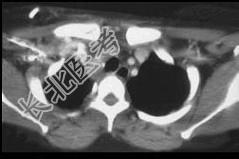

- 单项选择题男,33岁, 车祸后十余天,请结合影像学检查, 选出最可能的诊断 ( )

A、纵隔畸胎瘤

B、胸内甲状腺肿

C、胸腺瘤

D、淋巴瘤

E、纵隔血肿